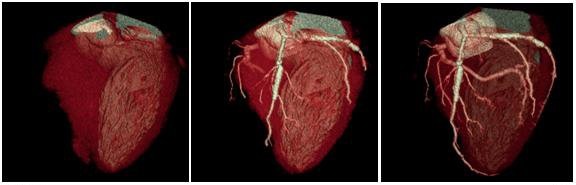

در این روش پرتوهای ایکس وارد بدن بیمار شده و رایانه، تصویر بسیار دقیقی از هر بخش تهیه میکند؛ بطورمثال امکان تهیه تصویر کامل از قلب در مدت تنها یک ضربان قلب فراهم میشود.

عروق، روده، قلب، مغز، استخوانها با جزئیات منحصربفردی به تصویر کشیده میشوند.